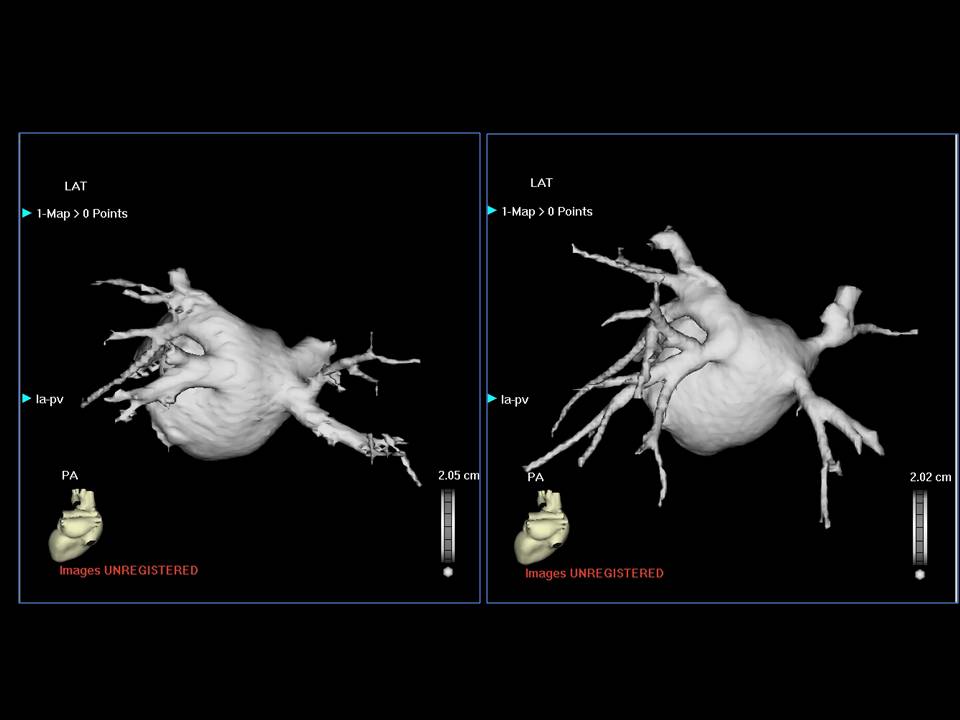

肺静脉隔离术难点